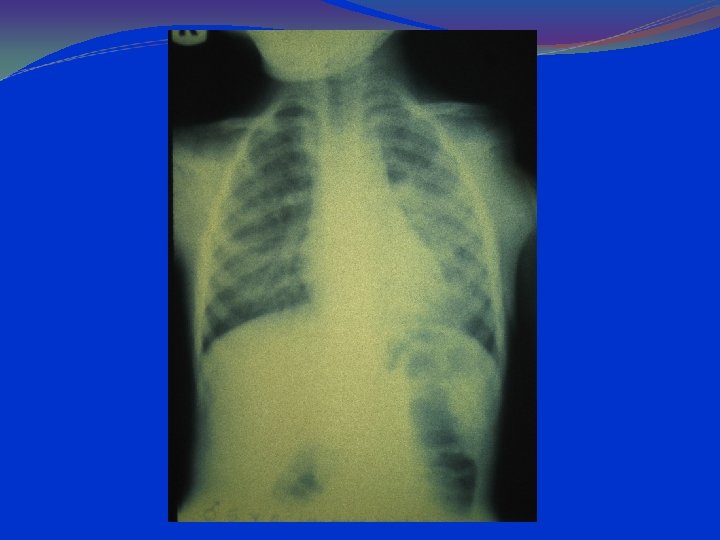

lung hyperinflation with a flattened diaphragm and bilateral atelectasis in the right apical and left basal regions

LABORATORY AND IMAGISTICS Complete blood count (CBC) with white blood cell (WBC) count within normal limits. 2/3 of the children have WBC counts of 10, 000 to 15, 000/μL. Most have 50 to 75% lymphocytes Serum chemistries may be affected in dehydration. Arterial blood gases (ABG) in severely ill patients, with mechanical ventilation. Chest radiographs should include anterior-posterior (AP) and lateral views. Hyperinflation and patchy infiltrates ; these findings are nonspecific and may be observed in asthma, viral or atypical pneumonia, and aspiration. Focal atelectasis Air trapping Flattened diaphragm Increased anteroposterior diameter